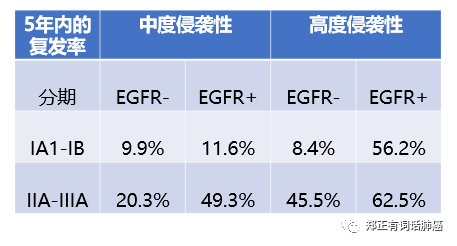

而将突变状态/分期情况以及病理亚型杂糅一起进行分析后,我们可以得到以下表格:

第二,就是该研究中在I期患者,绝大多数都是中/低度侵袭的,而表现为高度侵袭的患者并不多,其中,EGFR阴性39例,EGFR阳性只有9例。

因此,我个人的观点是,尽管EGFR突变可能在I期高侵袭人群带来不良的预后影响,但应该不至于引起高达56.2%的5年复发率。

毕竟样本量还是太小了。